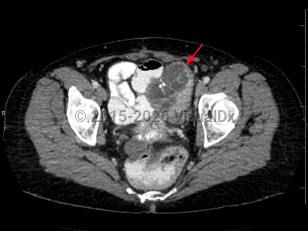

Psoas abscess

Abdominal aortic aneurysmAbdominal aortic aneurysm